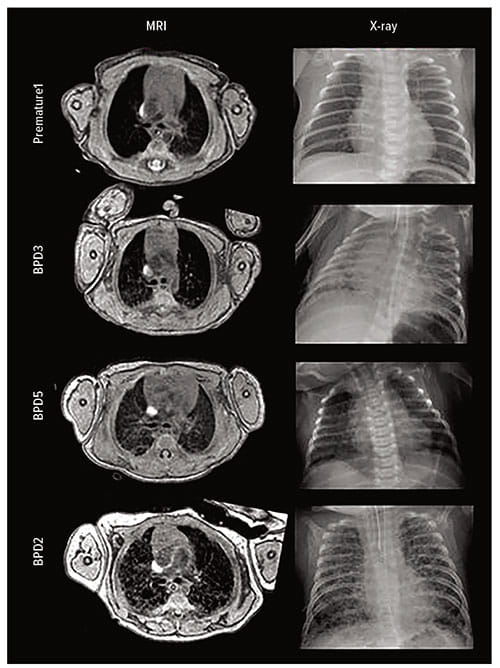

The team used a unique, small-footprint MRI scanner — developed at Cincinnati Children’s — that is located in the NICU. The team scanned six premature infants with BPD, six premature patients without BPD, and six full-term NICU patients.

A radiologist graded the images using a modified Ochiai score. The team also used segmentation and threshold analysis to quantify volumes of high- and low-signal intensity lung parenchyma.

The MRI detected quantifiable, significant differences in lung tissue between the three groups. “These methods,” the authors wrote, “could be implemented to individually phenotype disease, which may impact clinical care and predict future outcomes.”